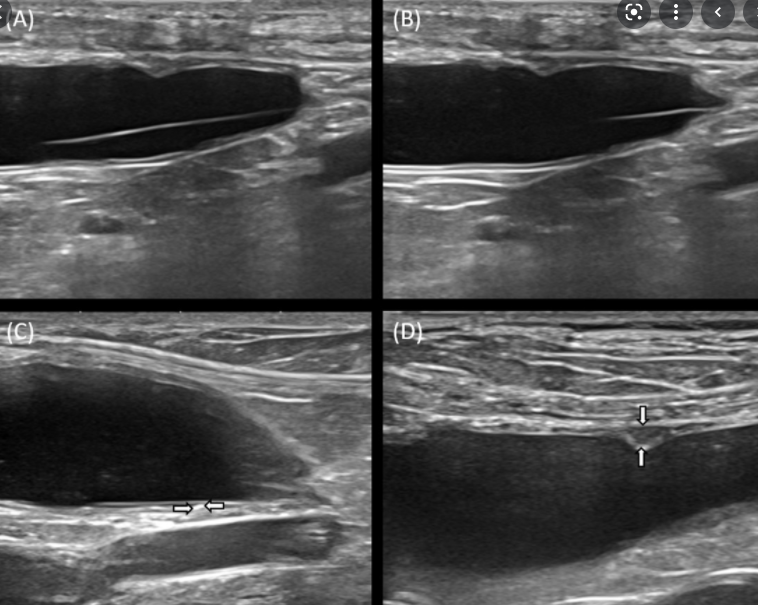

강아지 방광에 머리카락이?

어째서 방광내에 머리카락이 들어갔는지는 알 수 없지만

만성 방광염과 감염성 방광염의 원인이 되기 때문에 수술적 제거를 해줄 필요가 있다는 케이스 보고

방치하면 만성 방광염 뿐 아니라 결석도 생성되는 core가 될것으로 보임.